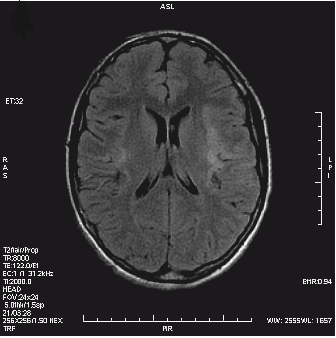

Które badanie zostało zarejestrowane na przedstawionym radiogramie?

Ilustracja do pytania 21

A. Jamy brzusznej wykonane poziomą wiązką promieniowania.

B. Płuc wykonane metodą Przybylskiego.

C. Układu moczowego z użyciem środka kontrastującego.

D. Dróg żółciowych metodą cholangiografii śródoperacyjnej.